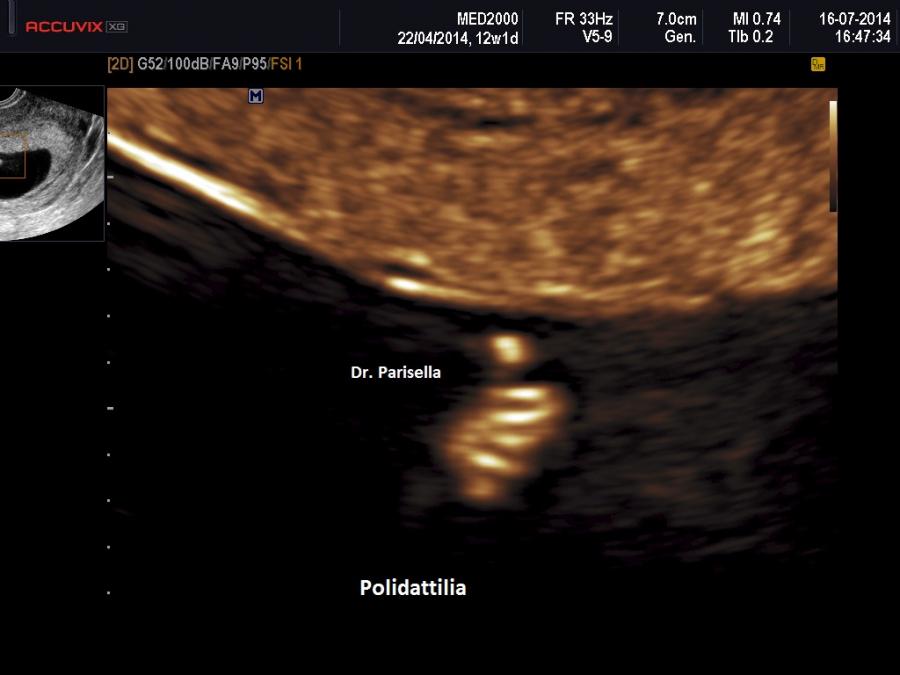

La MICROMELIA SEVERA e l’ IPOPLASIA TORACICA SEVERA (legata al torace stretto con coste corte) sono i segni principali presenti in tutte e quattro i tipi di SRPS e che indirizzano verso una corretta diagnosi. La POLIDATTILIA è presente nei primi due tipi, meno frequentemente nel tipo III, è assente nel tipo IV.

La MICROMELIA SEVERA e l’ IPOPLASIA TORACICA SEVERA (legata al torace stretto con coste corte) sono i segni principali che indirizzano verso una corretta diagnosi. La POLIDATTILIA, sempre presente, è di tipo postassiale ed interessa sia mani che piedi. Spesso è presente idrope.